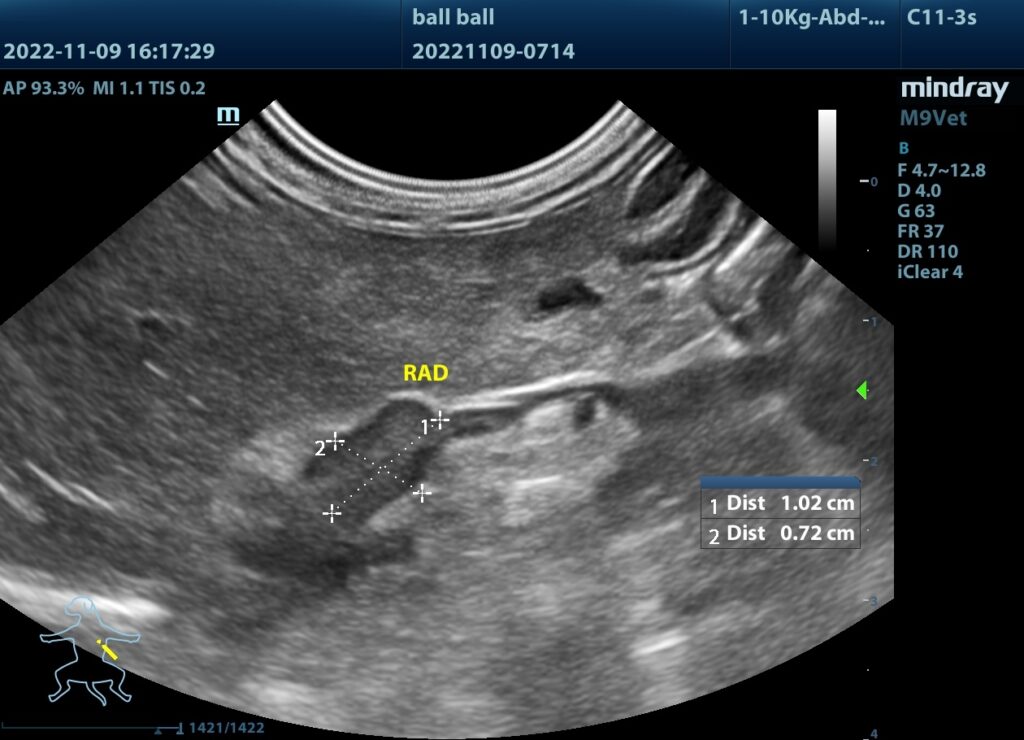

(2)超音波看見腫大的腎上腺。

腫大的腎上腺